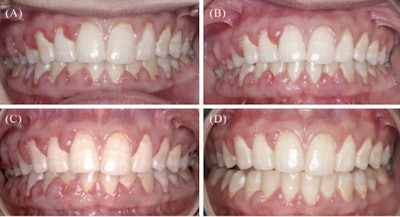

Clinical images. (A) At initial presentation (January 2024); (B) one month after initial debridement and oral hygiene instruction (February 2024); (C) following two more debridement sessions (April 2024); (D) one month following cessation of voclosporin therapy (June 2024).Images and captions courtesy of Tatakis. Licensed under CC BY-NC-ND 4.0.

In May 2024, she took her last dose of voclosporin. A month later, her gum overgrowth reduced significantly, her pain was gone, and her eating ability improved.